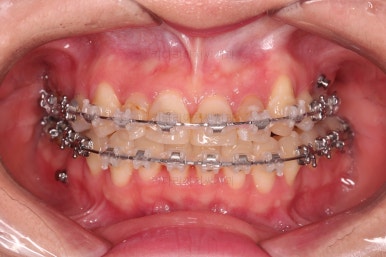

초진 시 입안의 모습입니다.

이미 썩어서 부러진 치아도 몇 개 보이고요.

많이 삐뚤어진 치아쪽은 양치가 힘들어 이미 많이 썩어 있는 상태에 덧니쪽은 잇몸도 많이 내려간 상태였습니다.

말그대로 교정치료 뿐만 아니라 전반적인 치료가 필요한 상황이었습니다.

덧니를 개선하기 위해서 추가적으로 작은 어금니를 발치했고요.

아랫니는 많이 삐뚤긴 했지만 옆라인, 턱의 크기 등 모든 걸 종합적으로 판단해 비발치로 진행하기로 했습니다.